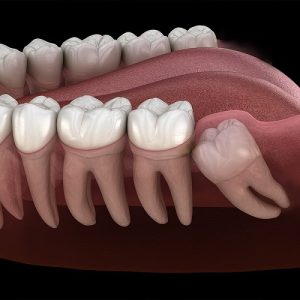

دندان عقل نهفته یکی از رایج ترین مسائل دندانی است که در سنین پایین برای هر انسانی پیش میاید در مواردی دندان عقل با کشیدن درست می شود ولی در مواردی نیاز به جراحی عقل نهفته می باشد که میتواند باعث درد، عفونت، و آسیب به دندانهای مجاور شود. در این مقاله، به بررسی کامل جراحی این دندانها میپردازیم در نهایت با تصمیم دندان پزشک مشخص می شود که مدل دندان عقل شما به چه شکل است و چگونه درمان می شود.

روش جراحی دندان عقل به صورت کلی بر اساس زاویه دندان و موقعیت ان در فک بررسی می شود. . دندانپزشکان و جراحان معمولاً نهفتگی را بر اساس زاویهای که دندان عقل نسبت به دندان مولر دوم مجاورش دارد، دستهبندی میکنند.

این مدل شایع ترین مدل در عقل نهفته است که عقل به مایل رو به جلو است، در زاویه با دندان مولر دوم قرار گرفته است. درباره جراحی این مدل هم معمولاً یکی از آسانترین انواع برای خارج کردن است، زیرا تاج دندان به سمت فضایی باز جهت دارد. ممکن است نیاز به برش و تقسیم دندان داشته باشد.

در این مدل نهفتگی دندان عقل در وضعیت صحیح عمودی قرار دارد، اما به دلیل کمبود فضای کافی، قادر به بیرون آمدن کامل نیست و زیر لثه یا استخوان گیر کرده است. پیچیدگی جراحی در این روش اگر فضای کمی در بالای دندان وجود داشته باشد، میتواند نسبتاً ساده باشد. با این حال، اگر دندان در عمق استخوان گیر کرده باشد، نیاز به برداشتن استخوان پوشاننده دارد.

دندان عقل کاملا به صورت 90 درجه و خوابیده است و معمولا به ریشه دندان دوم فشار می اورد و با درد زیاد همراه است. از نظر تکنیکی جراحی این مدل با پیچیدگی خاصی همراه است جراح تقریباً همیشه باید دندان را به چند قطعه تقسیم کند تا بتواند آن را تکه تکه خارج کند و از آسیب زدن به ریشه دندان مجاور جلوگیری نماید تا مشکل اضافه تری به ریشه دندان های دیگر نرسد.